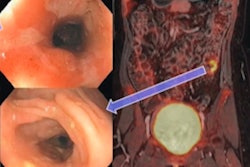

The patient underwent a flexible sigmoidoscopy to 20 cm from the anal verge, which demonstrated spontaneous bleeding and ulcerations throughout the examined mucosa, according to the report.

A subsequent PET/CT exam demonstrated abnormally increased F-18 DCFPyL uptake in the descending colon, sigmoid colon, and rectum in a distribution corresponding to the findings on endoscopy, the authors wrote.